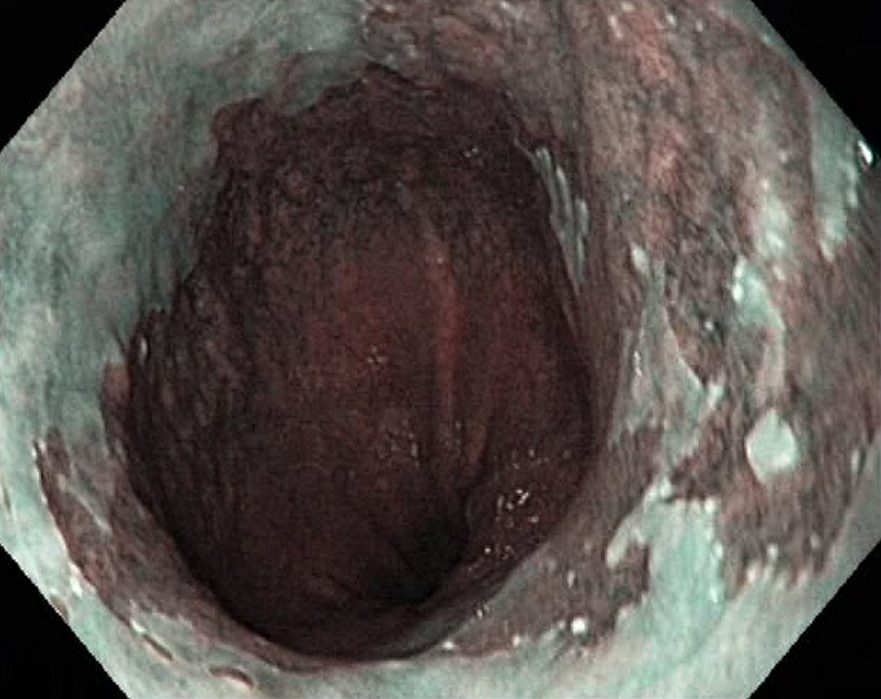

Barrets Oesophagus (NBI, Narrow Band Imaging)